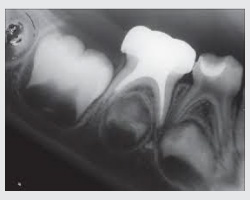

• Pit and Fissure Sealing is another preventive measure practiced in our clinic. The grooves of the teeth are filled, as to attract less plaque and to allow easy cleaning